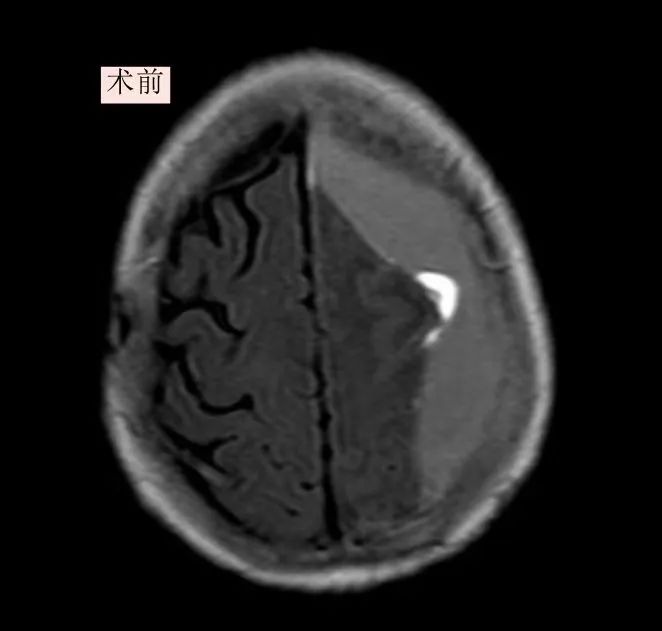

患者为85岁高龄女性,因"突发意识模糊、右侧肢体无力一周"入院。影像检查显示其左额颞顶存在慢性硬膜下血肿并伴有多层包膜分隔,血肿体积巨大压迫脑组织导致嗜睡、失语及右侧肢体肌力骤降至2级(正常为5级)。传统钻孔引流术难以彻底清除此类复杂的分隔血肿,而开颅手术对高龄患者风险极高。我院神经外科医护团队经过综合分析病情,并与患者家属充分沟通后,最终决定采用神经内镜微创技术实施精准干预。

术中,神经外科专家团队的李越主任医师主刀、陈思医师协同作战,在患者头部通过直径2厘米的微小骨洞,将神经内镜置入。在高清成像系统下,血肿腔内纵横交错的纤维分隔与黏稠积血展露无遗。他们凭借着精湛技艺,运用精细器械逐一离断分隔膜,各腔室血肿被彻底清除并精准止血。

手术历时90分钟,出血量不足30毫升。术后患者即刻恢复意识,可流畅对话,右侧肢体肌力显著提升至4级,次日即能自主进食并下床活动。